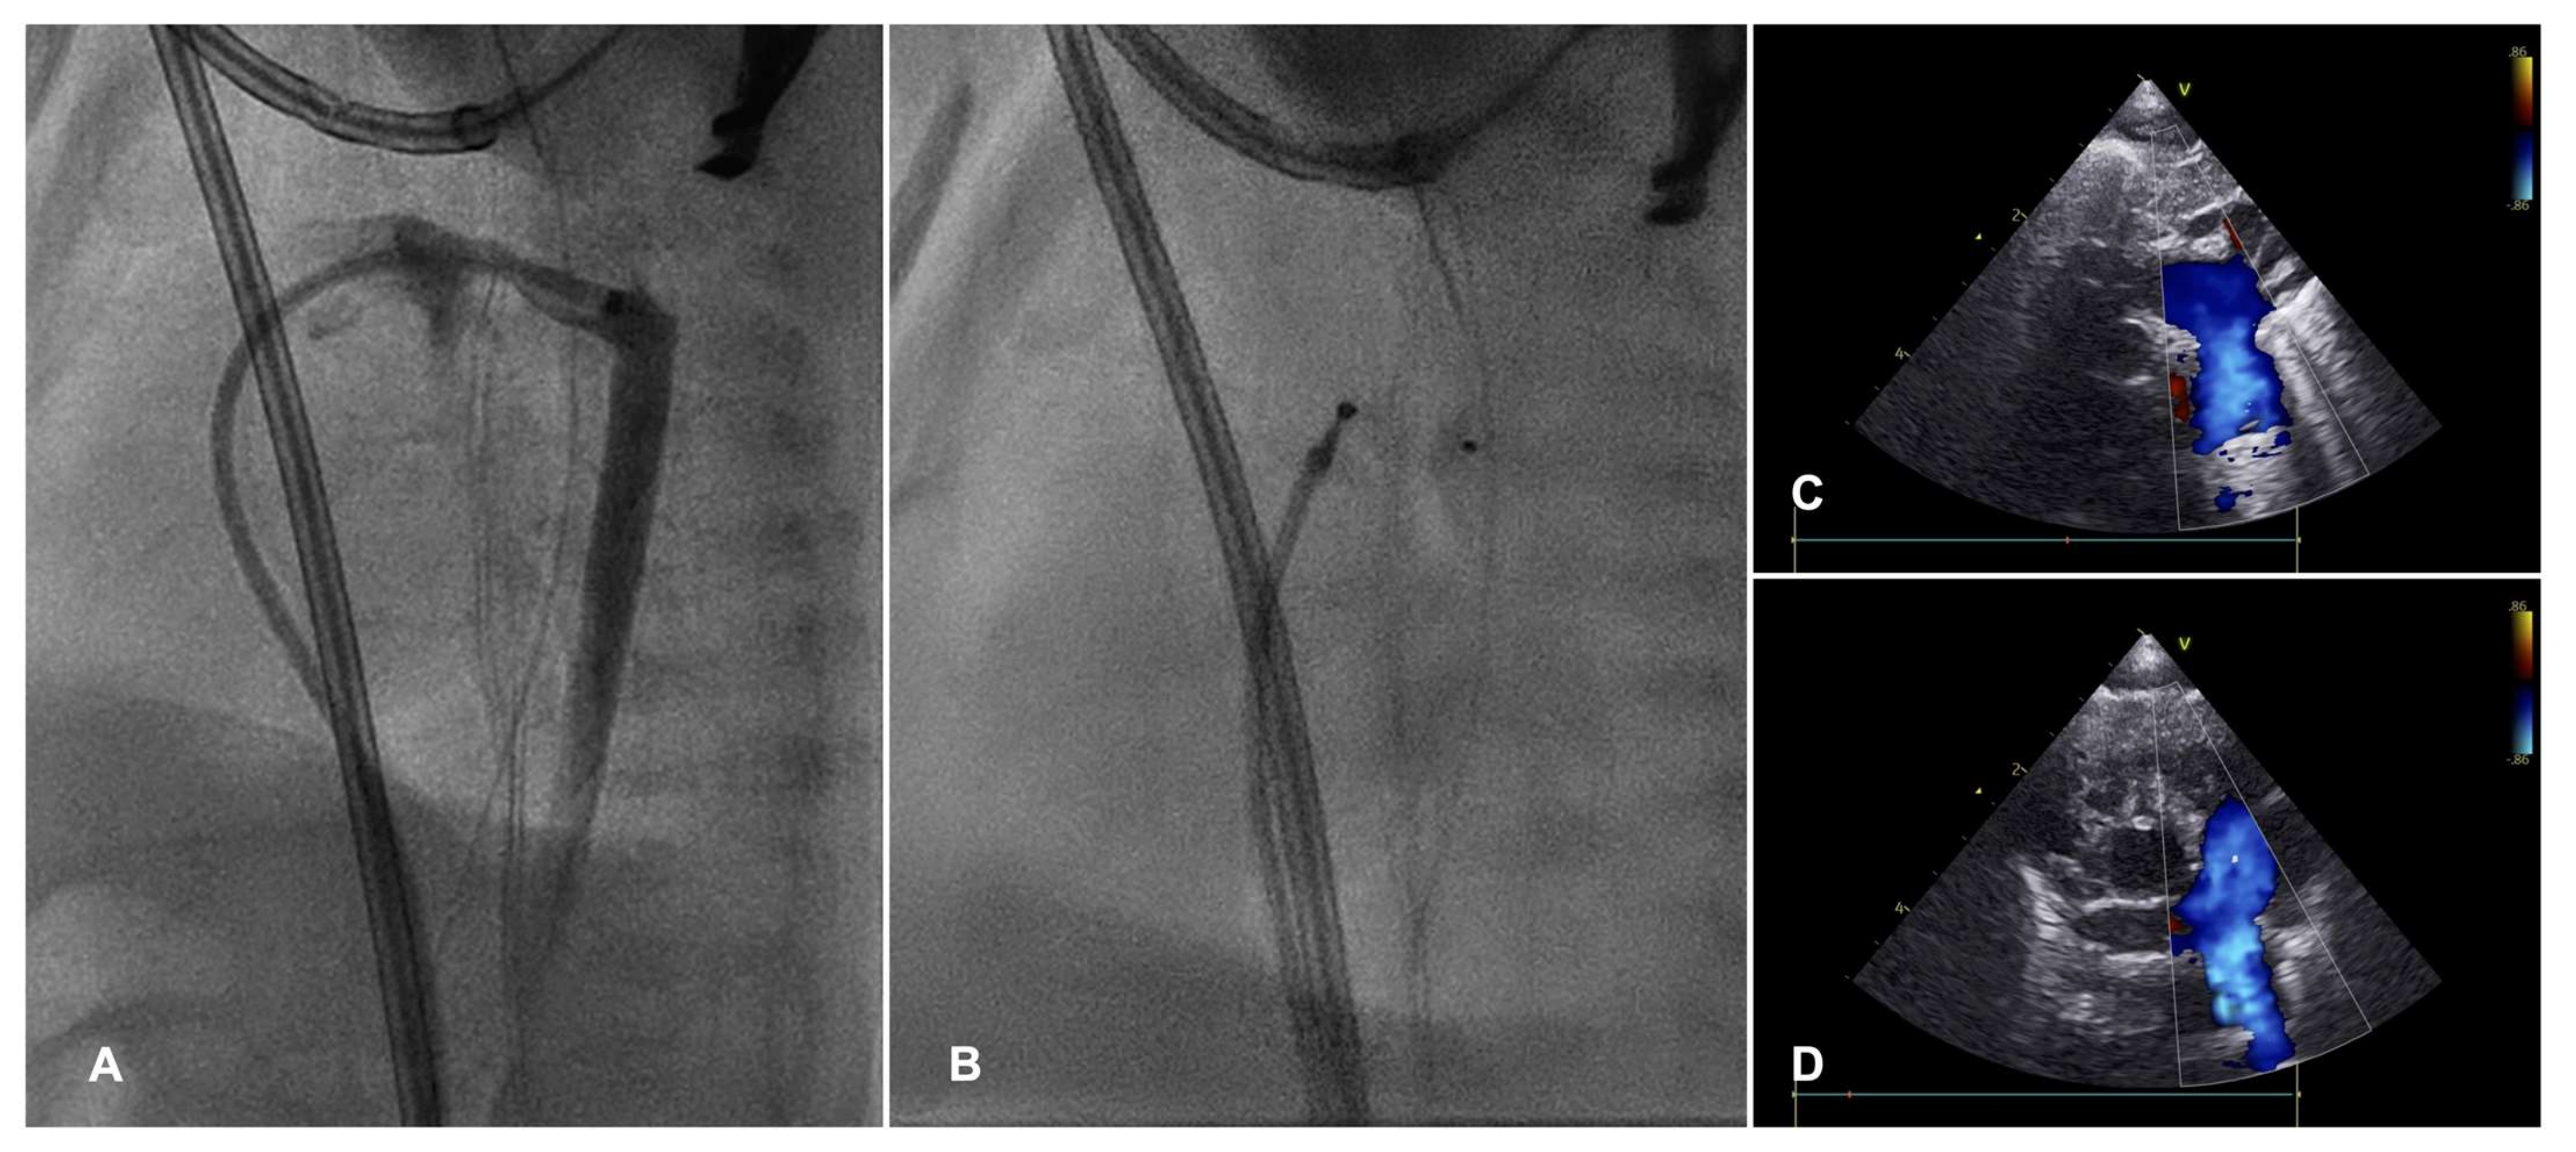

| BAA/stent implantation | CoAo and concomitant high surgical risk: prematurity, low BW, LV systolic dysfunction, LCO state | BAA: Acute aortic dissection, aortic aneurysm. Stent: in-stent stenosis, obstruction due to somatic growth. |

| Hybrid stage I palliation | HLHS complex (institutional preference, high surgical risk) | Stent migration, retrograde/antegrade aortic obstruction, inadequate PBF restriction. |